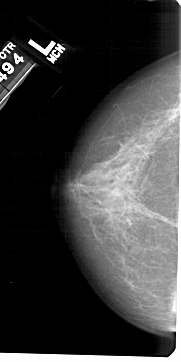

A_1520_1.LEFT_MLO

LEFT_MLO LINES 5491 PIXELS_PER_LINE 2716 BITS_PER_PIXEL 12 RESOLUTION 43.5 NON_OVERLAY